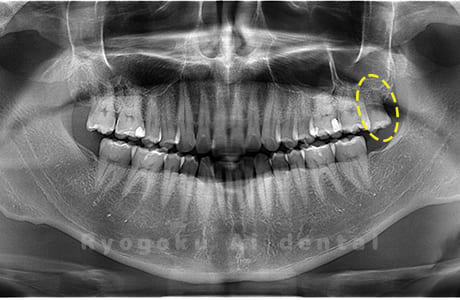

Case09

- 原因

- 下顎左の水平埋伏智歯

- 治療内容

- 下顎左の水平埋伏智歯を抜歯したケースです。

<リスク・副作用>

手術後は痛み、腫れ、痺れなどの副作用が生じる場合があります。